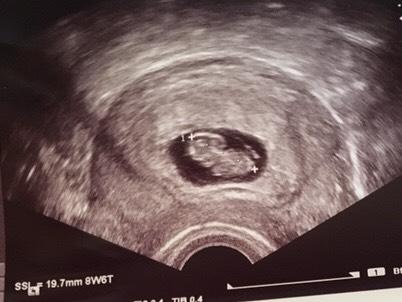

Ich war gestern beim Arzt und bekomme am Freitag meinen Mutterpass. Laut meinen Berrechnungen war ich gestern bei 9+0, laut Ärztin bei 8+6, also alles super

Ab heute dann 10. SSW.

Ich habe das kleine Herzchen schlagen sehen

Und als die Ärztin das kleine Würmchen messen wollte, hat es sich hin und her bewegt und wir mussten warten - voll niedlich

Ah, super, ich habe meinen Termin bei 8+5 (21.12) und werde mich sehr freuen, wenn ich dann auch schon so viel sehen kann wie du auf deinem US-Bild. Supergut!